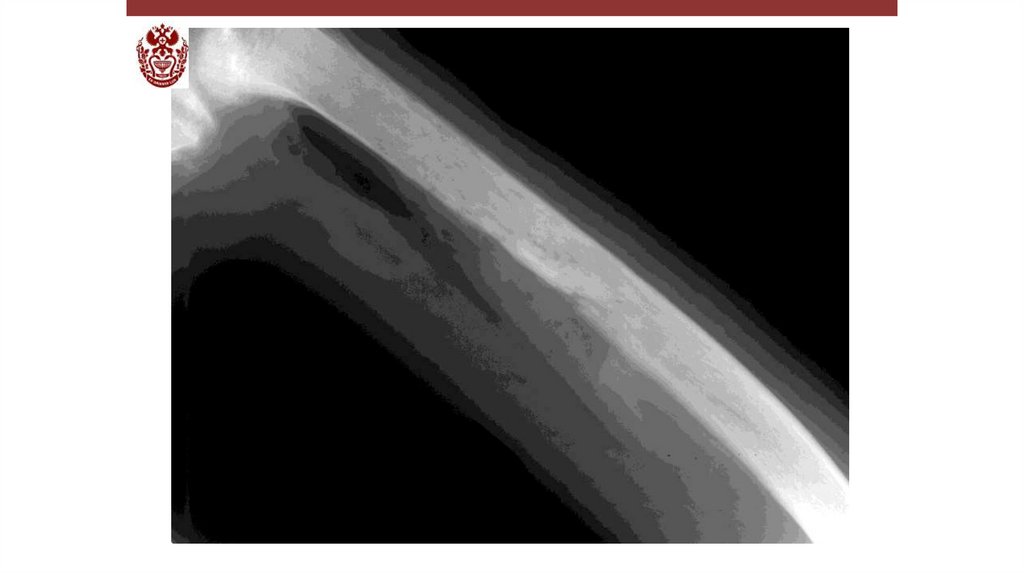

Воспалительные заболевания опорнодвигательного аппарата

«Воспалительные

заболевания опорнодвигательного аппарата»